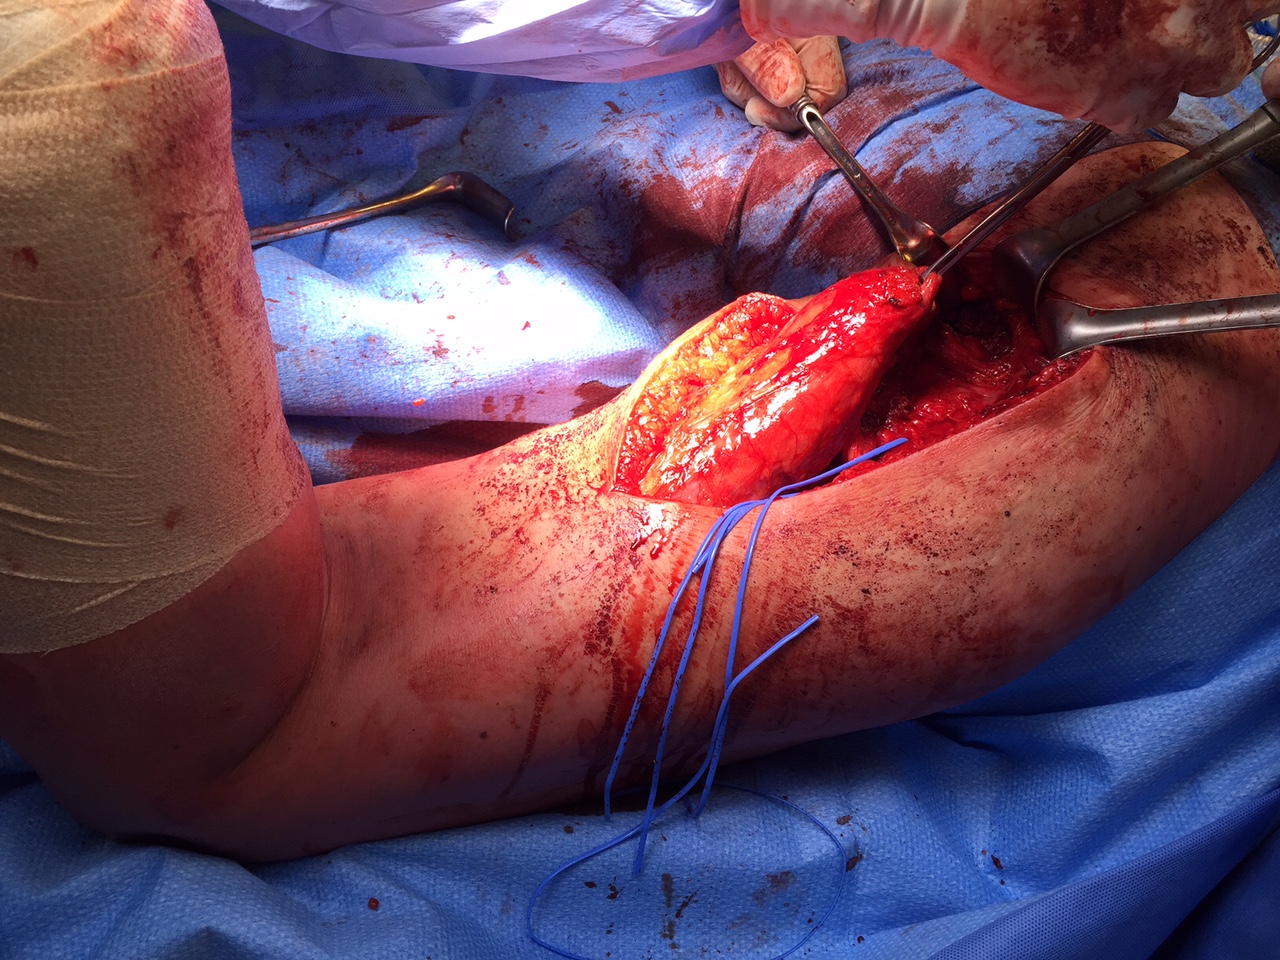

Multi-ligament knee injury (MLKI)

- 2 or more ligaments disrupted

Knee dislocation

- ACL + PCL + one of collaterals

High energy (MVA)

Low energy (sport)

- low energy has 5% arterial injury